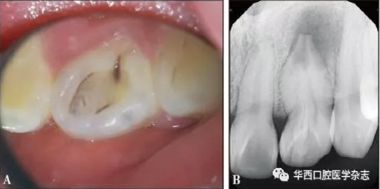

患者萬(wàn)某,女,21歲,2017年3月26日因左上前牙偶發(fā)脹痛不敢咬合數(shù)年于南昌大學(xué)附屬口腔醫(yī)院牙體牙髓科首診??趦?nèi)檢查:22牙唇側(cè)牙冠顏色、形態(tài)無(wú)異常,舌側(cè)中央內(nèi)陷,下方呈黑褐色,舌隆突處凹陷未蔓延至齦下(圖1A),唇舌側(cè)牙齦色澤形態(tài)質(zhì)地均無(wú)明顯異常,未見(jiàn)瘺管,叩診陽(yáng)性,牙周探診6個(gè)位點(diǎn)探診深度均小于3 mm,無(wú)附著喪失,無(wú)松動(dòng);牙髓電活力測(cè)試,12牙讀數(shù)17(上限64),21牙讀數(shù)20(上限64),22牙無(wú)反應(yīng);牙髓溫度測(cè)試,12牙、21牙冷熱診反應(yīng)一過(guò)性敏感,22牙冷熱診無(wú)反應(yīng)。X線片示22牙根管彎曲,牙冠內(nèi)陷從釉質(zhì)延續(xù)至根中1/3,主根管中央有一“內(nèi)陷小牙”高密度影結(jié)構(gòu),內(nèi)陷組織遠(yuǎn)中與主根管間可見(jiàn)明顯間隙,根尖孔粗大,根尖區(qū)為邊界不規(guī)則低密度影像,未見(jiàn)牙槽嵴頂處骨高度吸收異常(圖1B)。

A:口內(nèi)照;B:X線片。

圖 1 治療前情況